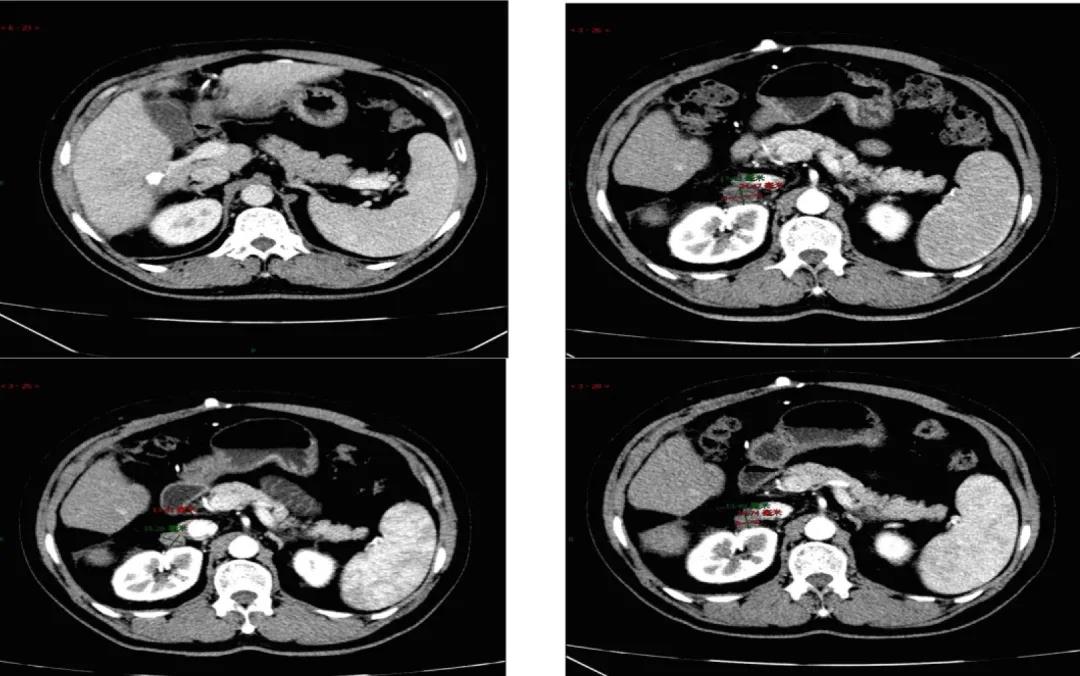

2019年9月21日患者出现乏力,纳差加重,体力下降。复查CT发现肝内病灶稳定,但右侧腹膜后淋巴结增大。疗效评价:疾病进展(PD;图2)。ECOG评分:1分。肝功能良好。2019年9月24日更换为口服瑞戈非尼片160mg QD,服3周停1周,4周为1周期。不良反应包括:胃肠道刺激,恶心,纳差,偶有呕吐,肌肉疼痛,乏力,皮肤粘膜反应,高血压轻到中度,给予硝苯地平缓释片控制血压,吗丁啉促进胃动力,奥美拉唑口服保护胃黏膜,间断使用芬必得控制肌肉疼痛等对症处理措施。耐受不好时偶有自行减量为120mg,但非连续发生。2019年11月19日,复查肝内病灶稳定,腹膜后淋巴结稳定。2020年2月5日,复查肝病灶稳定,腹膜后淋巴结缩小,疗效评价为部分缓解(PR;图3)。